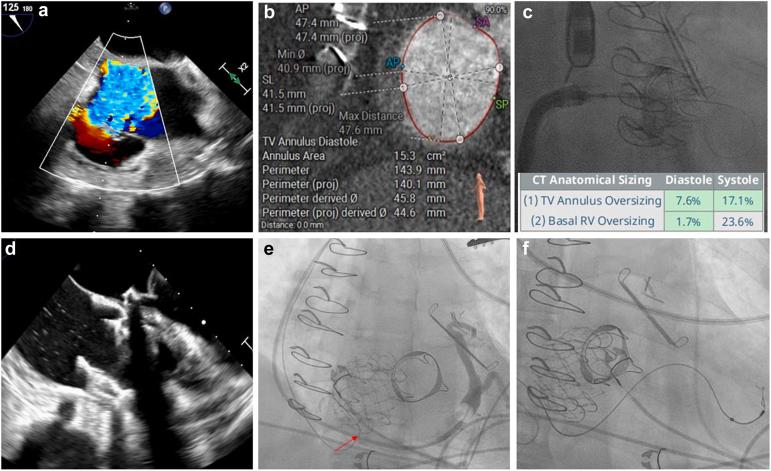

心脏植入式电子设备与使用EVOQUE系统的经导管三尖瓣置换术:一个强调手术及管理注意事项的病例回顾系列

Cardiac Implantable Electronic Devices and Transcatheter Tricuspid Valve Replacement With the EVOQUE System: A Case-Review Series Highlighting Procedural and Management Considerations.

Severe, untreated tricuspid regurgitation is associated with worse clinical outcomes. While isolated tricuspid valve (TV) surgery has been linked to poor long-term outcomes, transcatheter TV therapies, including edge-to-edge repair and transcatheter tricuspid valve replacement (TTVR), have emerged as effective alternatives and have been shown to improve outcomes, leading to their regulatory approval in the United States. Conduction system abnormalities are commonly seen among patients undergoing TTVR due to the close proximity of the atrioventricular node and the His bundle to the TV annulus. In the TRISCEND II (Transcatheter Tricuspid Valve Replacement: Pivotal Clinical Investigation of Safety and Clinical Efficacy Using a Novel Device) trial, 38% of the patients had prior cardiac implantable electronic devices (CIEDs), while 25% of patients developed new conduction abnormalities necessitating implantation of new CIEDs. Concerns exist regarding trapping existing CIED leads during TTVR. Similarly, transvenous permanent pacemaker implantation post-TTVR has been reported to be associated with valve dysfunction. In this case-based narrative review, we describe case examples of patients with prior CIEDs undergoing TTVR and conduction abnormalities post-TTVR needing a new permanent pacemaker and discuss potential periprocedural strategies for optimal outcomes. Electrophysiologists specializing in periprocedural management of CIEDs, including lead extraction and post-TTVR device management, play a crucial role and should be part of a comprehensive heart team approach for optimal outcomes.

摘要